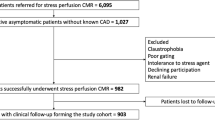

Of the 35,280 patients referred for stress CMR during the inclusion period, 1584 (4.5%) patients were referred for dipyridamole vasodilator stress CMR because of a first inconclusive noninvasive stress test. Among those, 1563 (98.7%) completed the stress protocol, as detailed in the flowchart (Fig. 1). Of the 1563 patients who successfully underwent stress CMR, the diagnosis of ischemia was inconclusive in 24 patients (1.5%) due to nondiagnostic image quality, arrythmias or artifacts. Out of these 1563 patients, 61 failed to respond to dipyridamole injection as assessed by the rate-pressure product (3.9%). No patient died during or shortly after CMR, and detailed safety results are presented in Additional file 5. Overall, 1402 patients completed the clinical follow-up and constituted our study cohort. Baseline subject characteristics and baseline CMR data are shown in Table 1. Among those 1402 patients (66.7% male, 69.5 ± 11.0 years), 58.4% had dyslipidemia, 57.6% had hypertension, 32.7% had diabetes mellitus, 30.7% had obesity, 27.9% had a family history of CAD and 24.0% were smokers. Overall, 727 (51.9%) patients had known CAD. Of note, 247 (17.6%) of patients were in atrial fibrillation or supraventricular arrhythmia. Regarding the first inconclusive stress test, 702 (50.1%) patients had a prior inconclusive stress echocardiography, 612 (43.7%) a prior inconclusive SPECT (147 dipyridamole SPECT) and 88 (6.3%) a prior inconclusive exercise ECG testing. The two main reasons for an inconclusive stress test were poor image quality (68%) and sub-maximal exercise (29%).